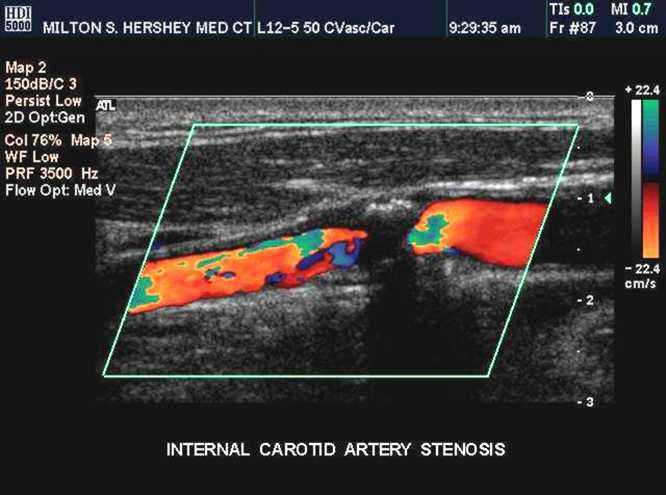

颈动脉彩超是颈动脉斑块的常规检查方法,可对斑块进行厚度和长度的测量,根据回声的性质对斑块成分进行初步的判断。除了超声,还有CT、核磁共振、血管造影等,都可以检查颈动脉狭窄。